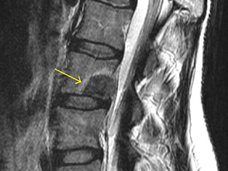

Targeted Radiation Reduces Pain from Cancer Metastases in the Spine

For some patients with painful spinal metastases from advanced cancer, a type of precise, high-dose radiation therapy—called stereotactic body radiation therapy (SBRT)—may be a highly effective way to relieve that pain, clinical trial results show.